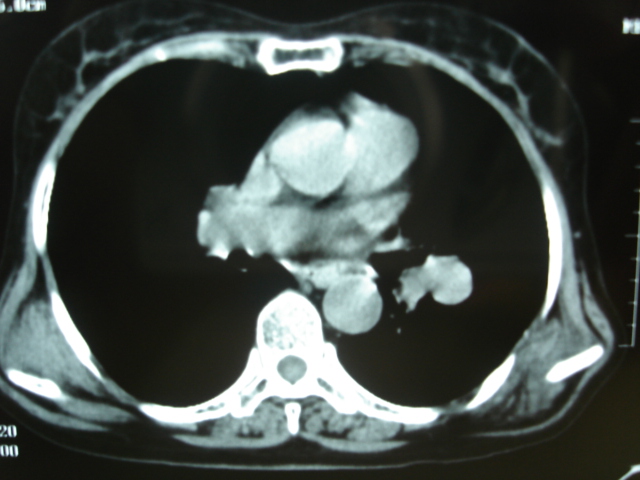

以下是引用卜一在2009-9-7 19:51:00的发言:[br][br] 1 左侧胸内甲状腺占位-多考虑甲状腺腺瘤! 2、左肺门占位-建议增强扫描以便明确性质。 3 慢支并感染! [br]

以下是引用shibing在2009-9-7 20:40:00的发言:[br]左侧胸内甲状腺占位-多考虑甲状腺腺瘤! 2、左肺门占位-建议增强扫描以便明确性质。 3 慢支并感染! [br]